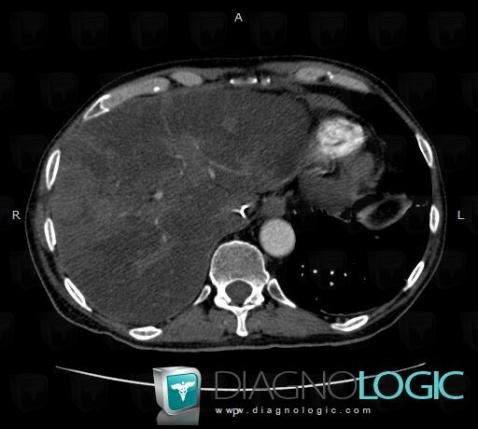

Fatty infiltration, Liver, CT

Here is the specific information in the key image above:

- Diagnosis Fatty infiltration, Location(s) Liver, with gamuts